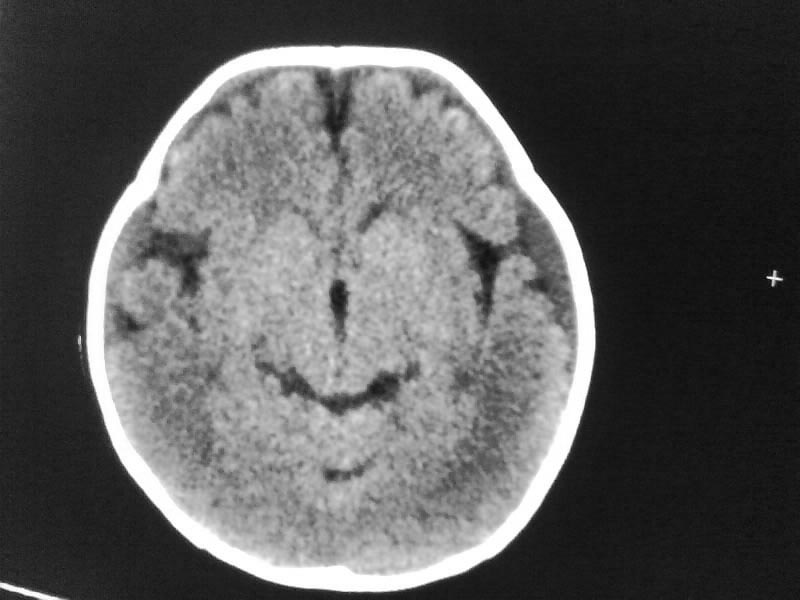

以下是引用随光逐影在2009-4-15 17:59:00的发言:[br]1)右侧额颞顶部硬膜下血肿。2)外部性脑积水。